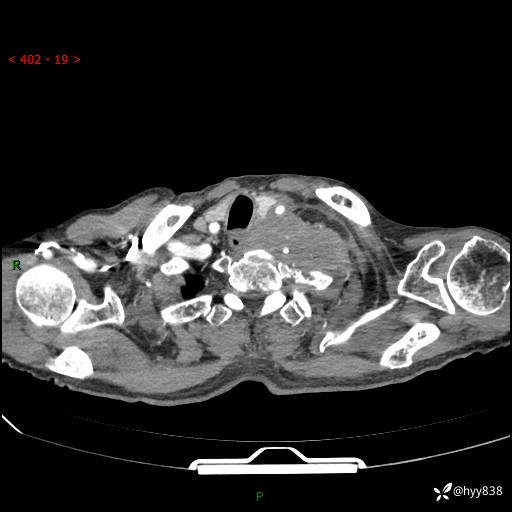

老年男性,气促5月,胸背痛2月。发现肺尖较大肿块,摧枯拉朽之势---结果公布~

现病史:患者于5月前饮酒后突发静息状态下气促不适,无胸闷、胸痛、发热、咳嗽、咳痰等不适,于当地第五人民医院及我院就诊,输液治疗后(具体不详)后气促稍缓解,遂出院后自行口服中草药治疗。近2月出现胸背痛,伴左上肢疼痛、乏力、感觉异常,稍有咳嗽、咳痰,咳黄痰、痰液粘稠,无咳血。为进一步诊治来我院。

胸部CT增强扫描(外院平扫)